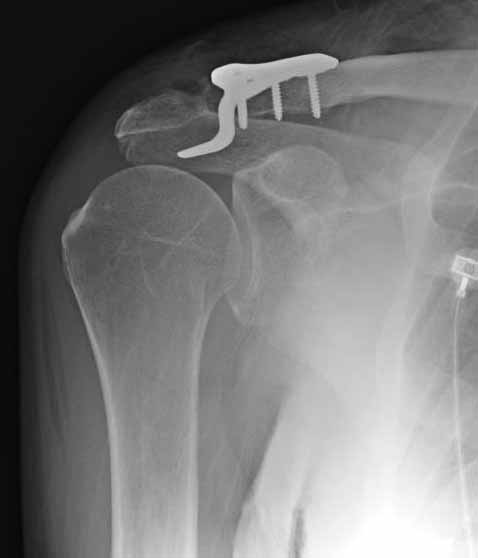

Но это не помешало успешно пациента прооперировать.

1.JPG

foto

2.JPG

foto 3

3.JPG

foto 4

4.JPG

foto 5

коллаж у меня не получился, пришлось отдельно рентгенограммы присоединить :-))

5.JPG

На конференции EFORT в Копенгагене поднимался вопрос о пластинах для остеосинтеза ключицы с крючком. Не имею возможность осветить все что там услышал. Но у меня появилось понимание о импиджмент синдроме, о необходимой длине крючка, о правильном позиционировании пластины, о лизисе акромиона и т.д.

Мне кажется что если понять принципы, то можно использовать и короткую пластину. Что мы с успехом применяли раньше и применяем сейчас, но уже более осознанно. В вашем случае Серж, у меня стойкое ощущение, что необходима дополнительная иммобилизация, так как неправильно выбрано место введения крючка и при ранней нагрузке пластину просто вырвет. Если вам несложно не могли бы вы продемонстрировать прямую и боковую проекцию и в более хорошем качестве. ИМХО

На чем у Вас обосновано" стойкое ощущение, что необходима дополнительная иммобилизация, так как неправильно выбрано место введения крючка"?

Теоретически можно использовать и короткую пластину. Но на операции дистальный отломок( акромиальный конец ключицы ) был коротким и оскольчатым, поэтому крючок и использование там блокированных винтов в пластине было очень уместно. Доступ - "сабельный удар". Точка введения крючка - сразу сзади от ключично-акромиального сустава. Если честно - больше внимания уделяли репозиции отломков и адекватному расположению пластины на ключице :-) крючок проверяли на прочность фиксации за акромион и полный объем движений в плечевом суставе. После операции рука на косынке, нагрузку ограничили. Снимки есть в нормальном разрешении, но здесь "размер файла не превышал 75 кб." Если есть необходимость залью в пикассу...